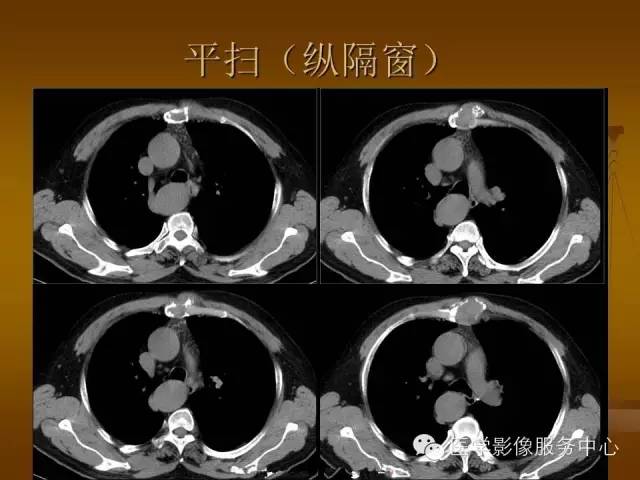

胸骨浆细胞骨髓瘤1例CT影像表现

特征性穿凿状、鼠咬状及蜂窝状骨质破坏,边缘清楚,骨质疏松,病理性骨折及软组织肿块等表现,骨质硬化及骨膜反应少见。

骨质破坏区完全为软组织取代,骨质膨胀,边界清楚,常突破骨皮质形成软组织肿块。